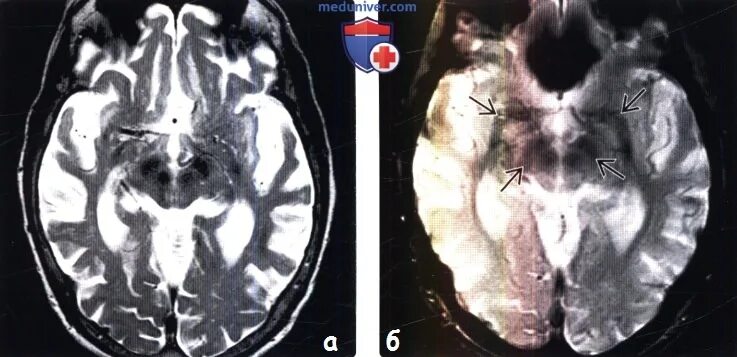

Диффузной биполушарной кортикальной атрофии